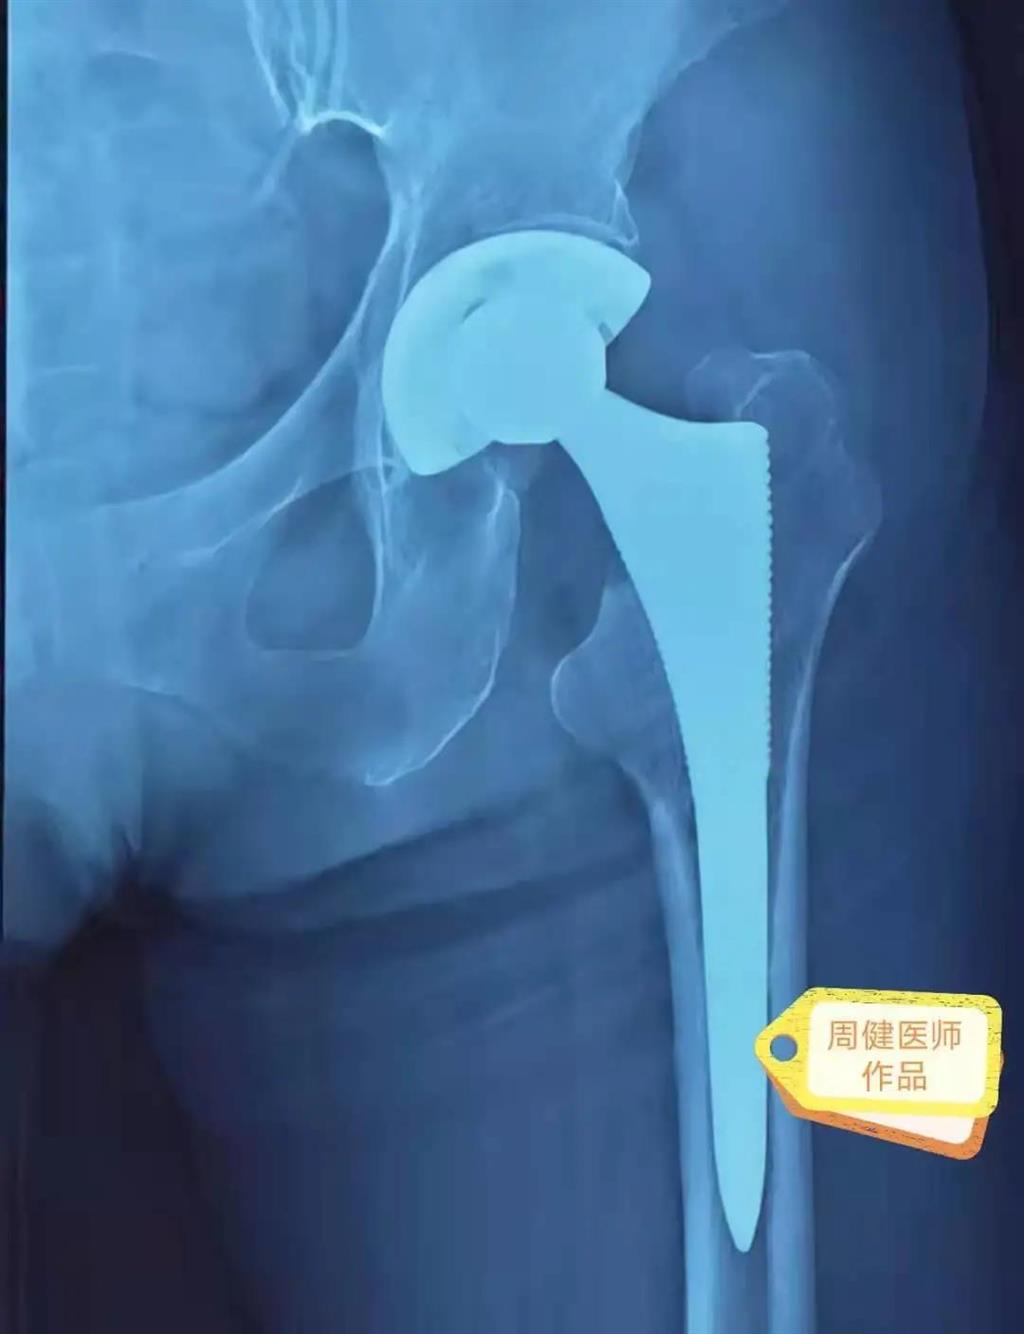

6月30日的“關(guān)節(jié)置換術(shù)”,患者是一位上了年紀(jì)的老人,苦于病痛折磨多年的他四處“求醫(yī)問藥”,最后在多位專家醫(yī)師及病友地力薦下選擇了和平國際醫(yī)院,在醫(yī)師團(tuán)隊“偷天換日”般的手術(shù)后,老人成功告別了苦纏多年的病痛。

周健說,這場“關(guān)節(jié)置換術(shù)”對于他們團(tuán)隊而言其實算是比較普通的手術(shù),因為做過很多同類的手術(shù),成功案例繁多,因此在手術(shù)操作上有較多地實操經(jīng)驗。“不過話雖如此,作為醫(yī)生我們對于每一場手術(shù)都會全力以赴,這是為醫(yī)者的職責(zé)也是義務(wù)。”